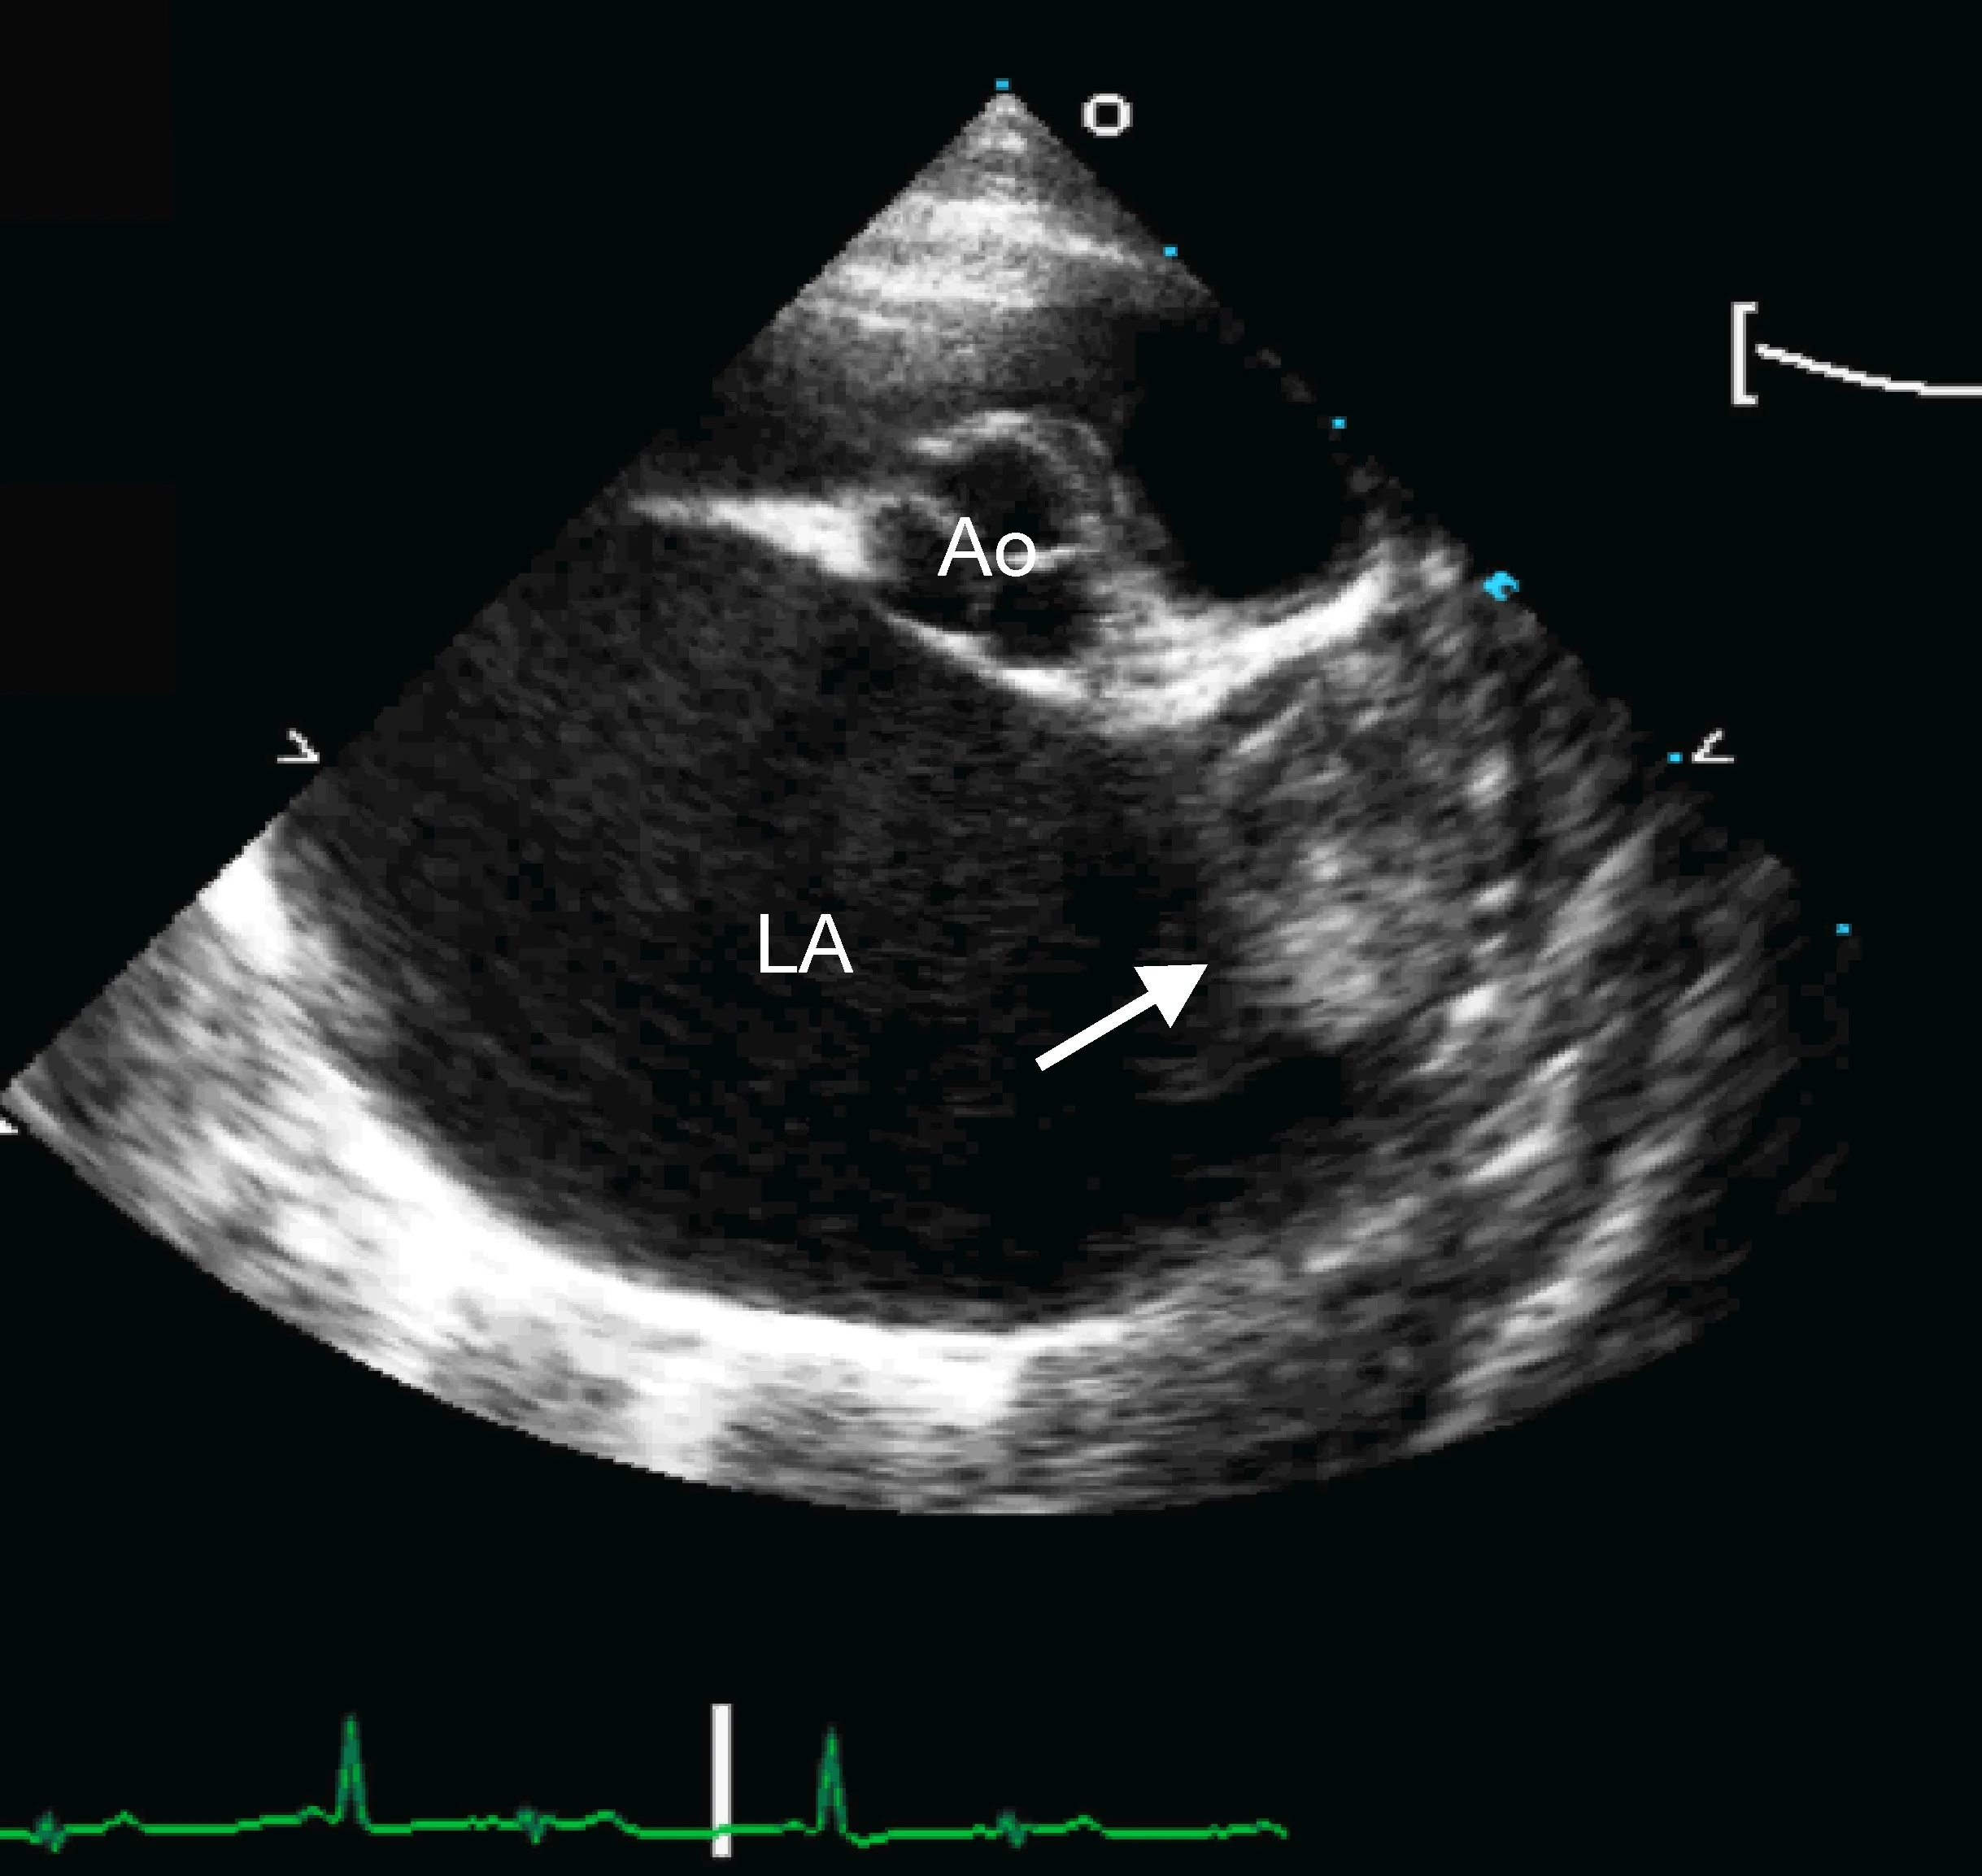

Marked left atrial enlargement was present on echocardiography after stabilization and pain management (see Treatment). A formed thrombus was apparent within the left auricle (Figure 4) and spontaneous echo contrast or smoke was present within the left atrium (Figure 5). This spontaneous echo contrast is often seen with marked chamber dilation and blood stasis; although its presence is associated with an increased risk for thrombus formation, it is not a result of a formed thrombus. Thickening of the left ventricular walls was also noted (Figure 6), which is consistent with underlying hypertrophic cardiomyopathy.

Right parasternal short-axis echocardiographic view of the heart base. The left atrium (LA) is markedly enlarged compared with the aorta (Ao). A thrombus is evident in the left auricle (arrow)